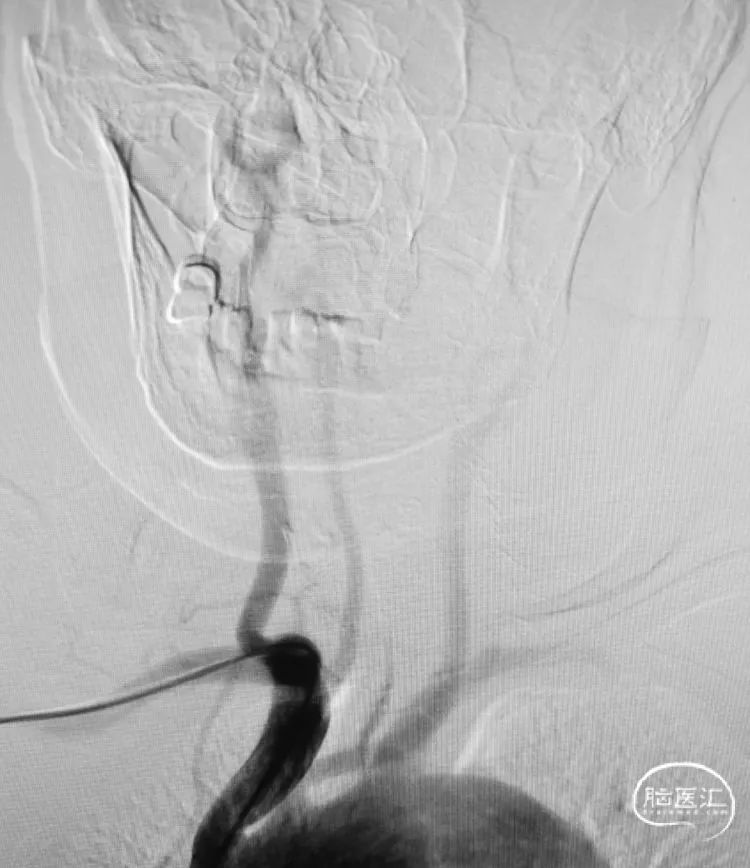

术前影像

这个弓型不好弄!果断使用6F 70长鞘。

颈总动脉更尴尬,是块硬骨头。